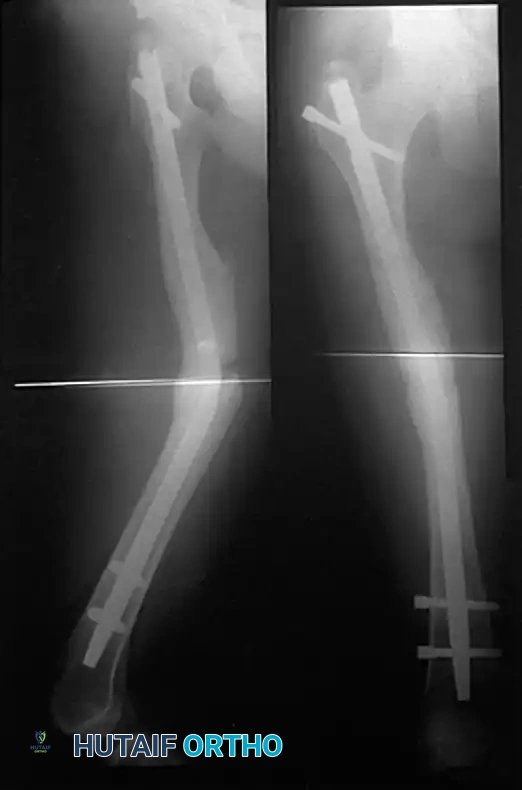

Intramedullary Nailing (The Gold Standard)

Internal fixation of femoral shaft fractures revolutionized trauma care following World War II with the introduction of the Küntscher nail. Today, interlocking intramedullary (IM) nailing is universally considered the treatment of choice for the vast majority of femoral shaft fractures.

In a young adult patient with a fracture through the isthmus of the medullary canal, a reamed, locked IM nail provides the ultimate biomechanical construct. It acts as a load-sharing device, allowing for early weight-bearing, a short hospital stay, rapid return of joint motion, and a high rate of union.

Distal and Proximal Locking

Locking the nail prevents shortening and rotational malalignment, which is especially critical in comminuted (AO Type B and C) fractures.